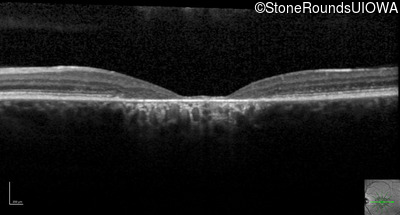

Optical Coherence Tomography - Left - 20/200 -2 sc

Exemplar / OCT Stack